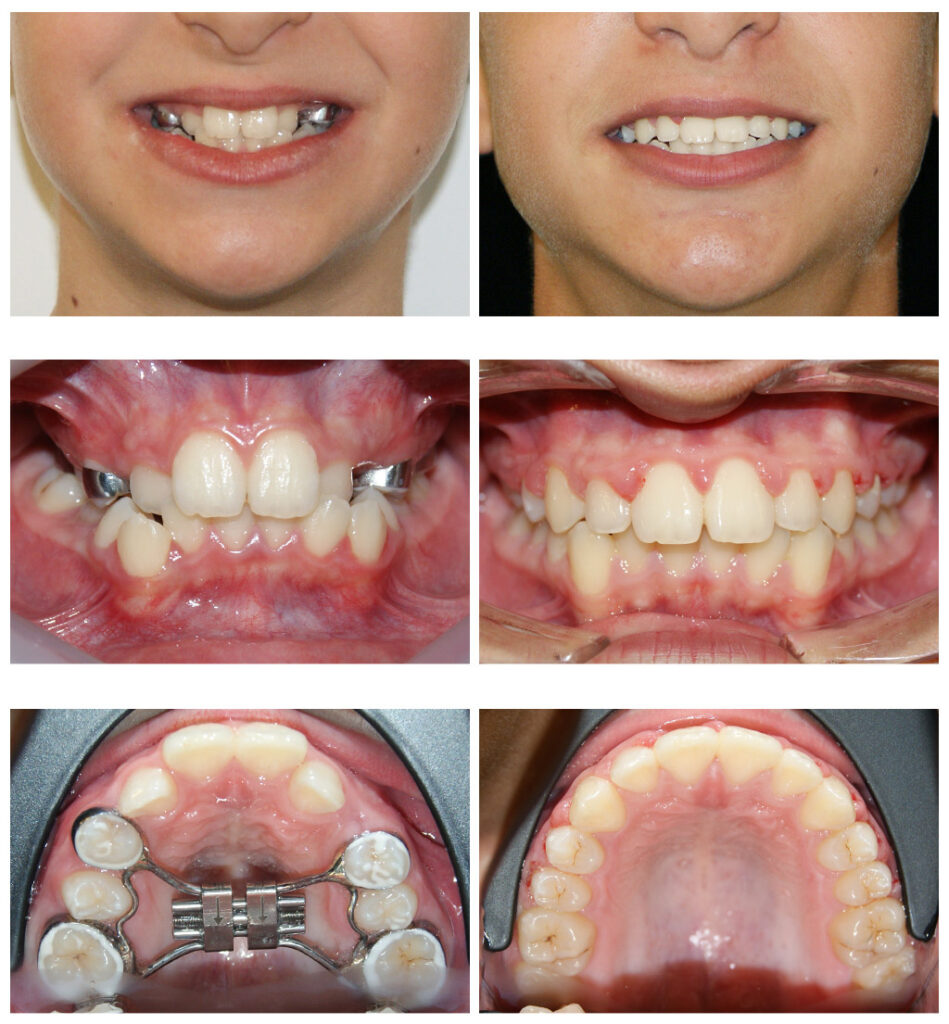

Corectarea muscaturii inverse cu forte extraorale – masca Delaire și disjunctor maxilar. Câteva luni pentru rezultate de care copilul se bucură întreaga viată

Corectarea muscaturii inverse cu forte extraorale – masca Delaire și disjunctor maxilar Alegem aparatul potrivit la vârsta potrivită

Corectare angrenaj invers